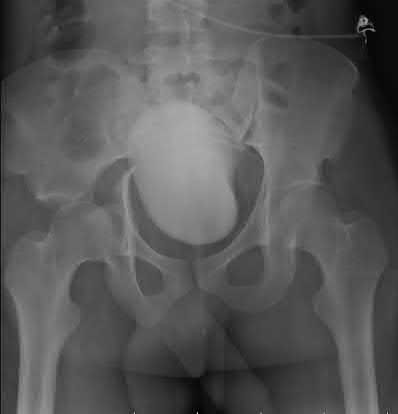

A 12-year-old obese boy presents with vague left thigh and knee pain. He is diagnosed with a Slipped Capital Femoral Epiphysis (SCFE) as seen in similar clinical scenarios.

During percutaneous in-situ fixation, unrecognized penetration of the guide wire into the hip joint occurs. What is the most likely specific complication resulting from this technical error?